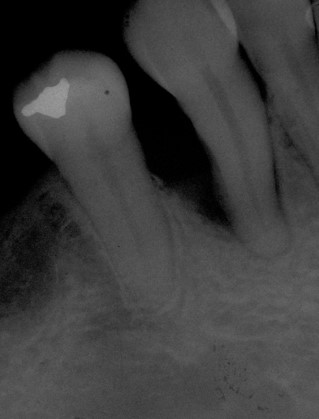

Fig 25. Post-treatment, healthy bone and ideal implant placement were observed radiographically.

Figure 25

Second-stage surgery involved uncovering the implant and finalizing the prosthetic treatment (Figure 24). The ultimate outcome represented a thickened biotype, healthy bone (Figure 25), and an inconspicuous implant-supported crown restoration (Figure 26).